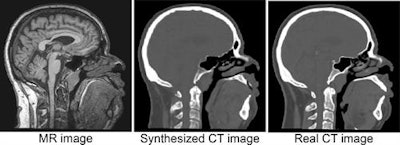

- Image-to-image synthesis. Images can be translated from one domain to another, e.g., synthesis of pseudo-CT images from brain MR and synthesis of routine-dose CT images from low-dose CT. Acquisition of certain images may be omitted to save time and reduce costs, patient discomfort, and CT radiation dose. The network can predict a Hounsfield unit value for each voxel in the MR image, and noise can be removed.